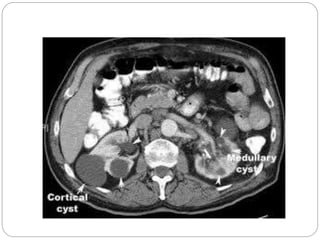

Renal /parapelvic Cyst

Parapelvic cyst

Severe hydronephrosis with

proximal hydro ureter

Moderate hydronephrosis on

right and severe on left

URINARY TRACT Renal /parapelvicCyst Severe Hydronephrosis/ Pelviureteric junction obstruction Cystic Wilm’s Tumour (rare) Urachal Cyst